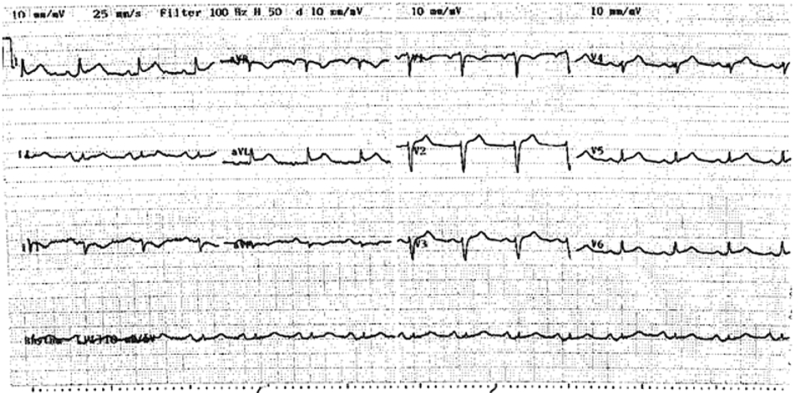

A 75-year-old woman presented with acute onset of discomfort in the chest, left scapula, neck and arm after being informed of the unexpected death of her son, and 2 days after undergoing an uncomplicated laparoscopic cholecystectomy. Her medical history included Graves’ disease and a hysterectomy. She had no modifiable risk factors for coronary artery disease. Examination revealed a heart rate of 90 beats per minute and a blood pressure of 120/80 mmHg, with no evidence of acute pulmonary oedema. At presentation, an electrocardiogram demonstrated 1–2 mm ST elevation in leads V1–V6, I and aVL (Box 1).